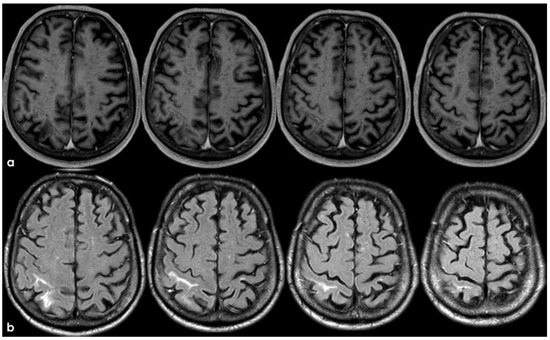

2. December 2013: Sulcal SAH and TFNEs